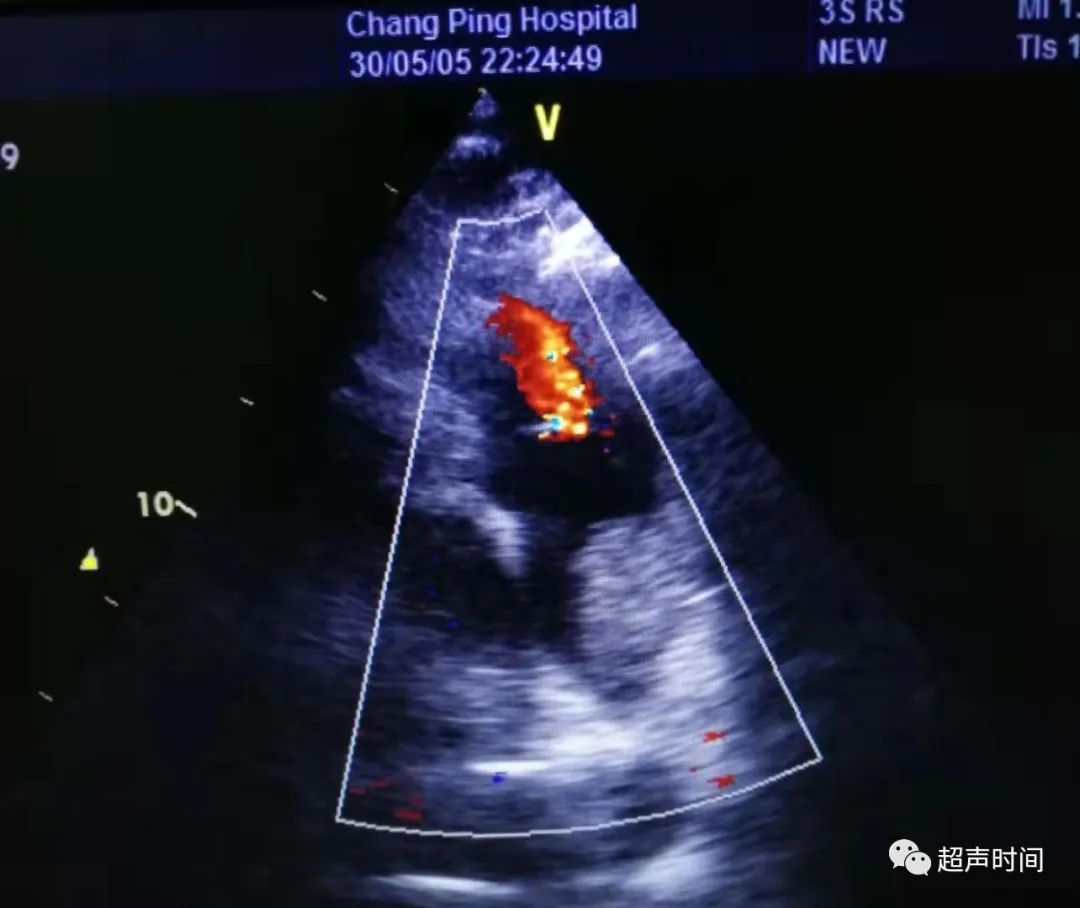

急诊床旁心脏超声所见如下:

图 3 和图 4 大动脉短轴切面显示右心房右心室增大,肺动脉扩张,左心室呈 D 型,充盈受限

此时,根据超声所见并结合临床,考虑可能存在肺栓塞。于是再回去仔细检查大动脉短轴切面,果不其然: